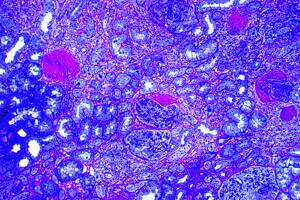

Fig# 11. GNMB I. CA 1, CC2, y DM (OMS VB). GNMB y proliferacion mesangial y nefrosclerosis diabética (OMS ?). MOAR 400X.